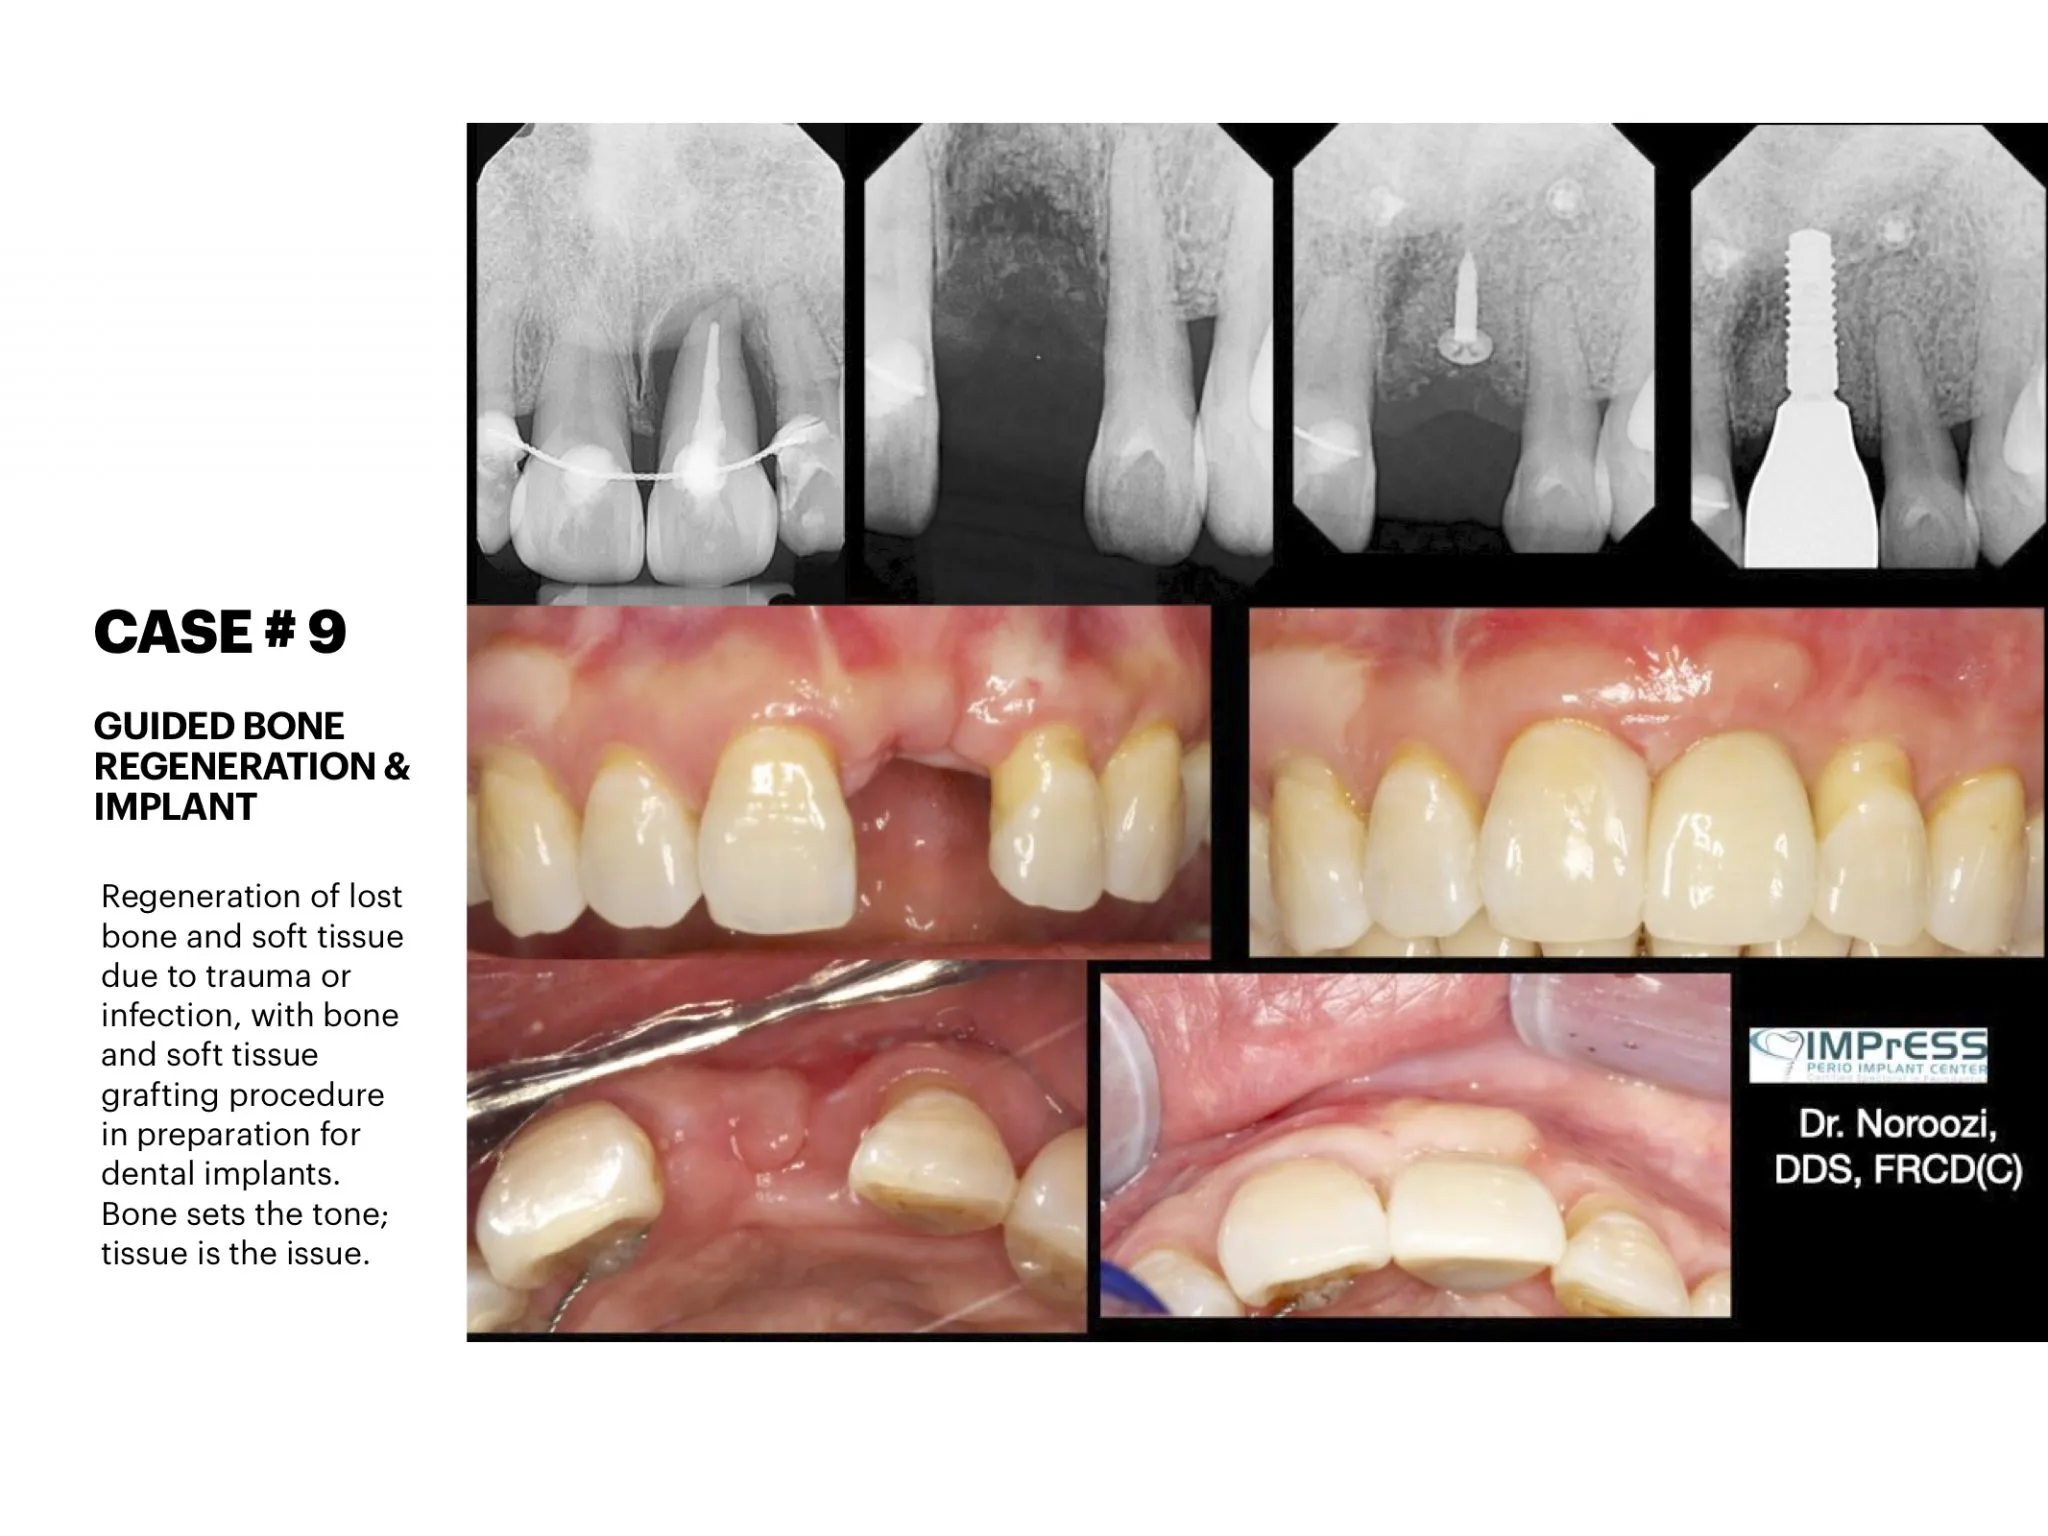

Before & Afters of Dental Implant Patients

Complete Dental Implant Cases Gallery

General Disclaimer: The results in the photographs are examples only and do not imply any certainty of the result of a procedure, and all outcomes are subject to the circumstances of the individual patient.